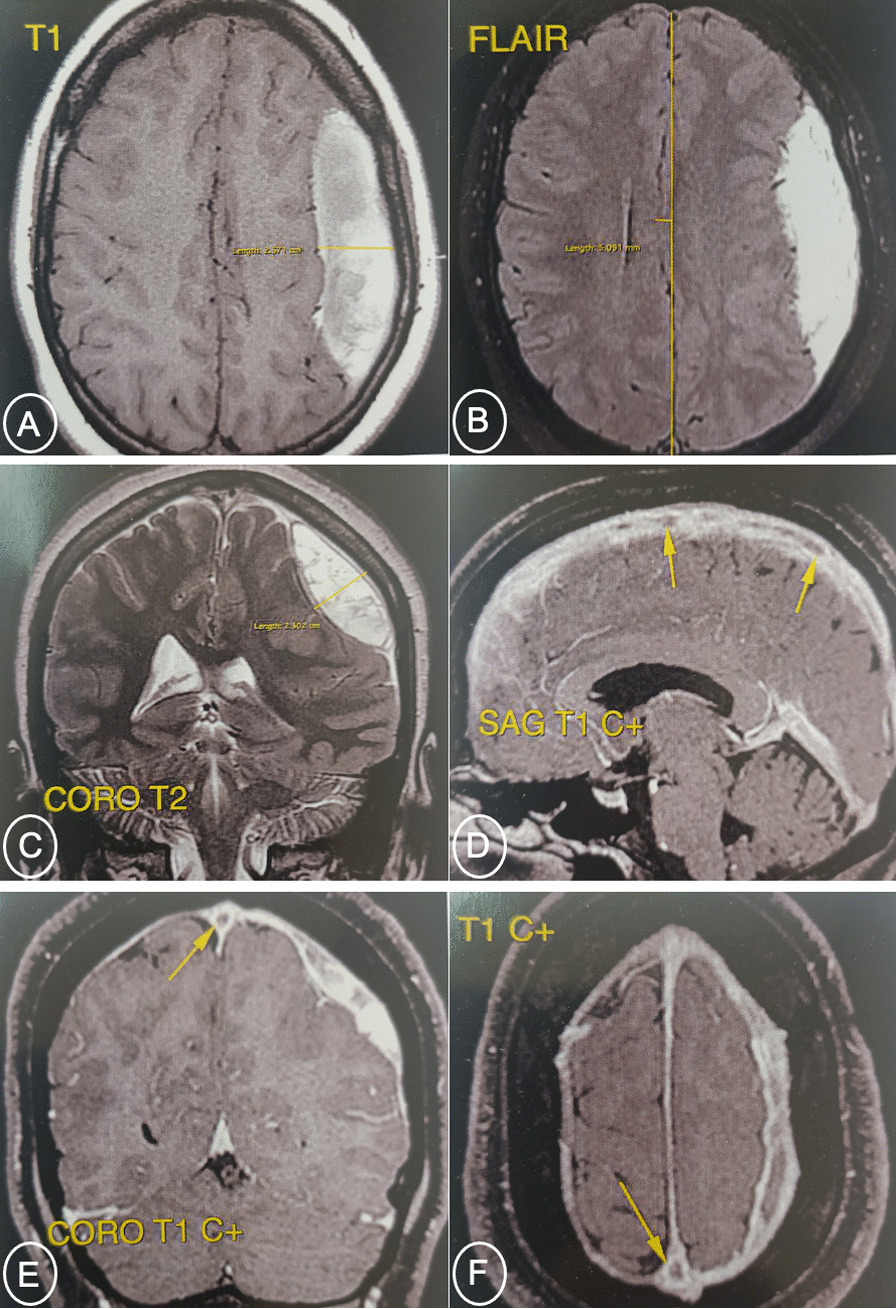

Contrast-enhanced brain MRI revealed cerebral venous thrombosis of the superior longitudinal sinus (empty delta sign) with a 25 mm thick left fronto-parietal chronic subdural hematoma resulting in a 5 mm midline deviation to the right side (Fig. 1).

Initial contrast-enhanced brain MRI. A, B and C SDH hyperintense on T1, isointense on T2-FLAIR. D, E and F Endoluminal defect related to superior longitudinal sinus thrombosis